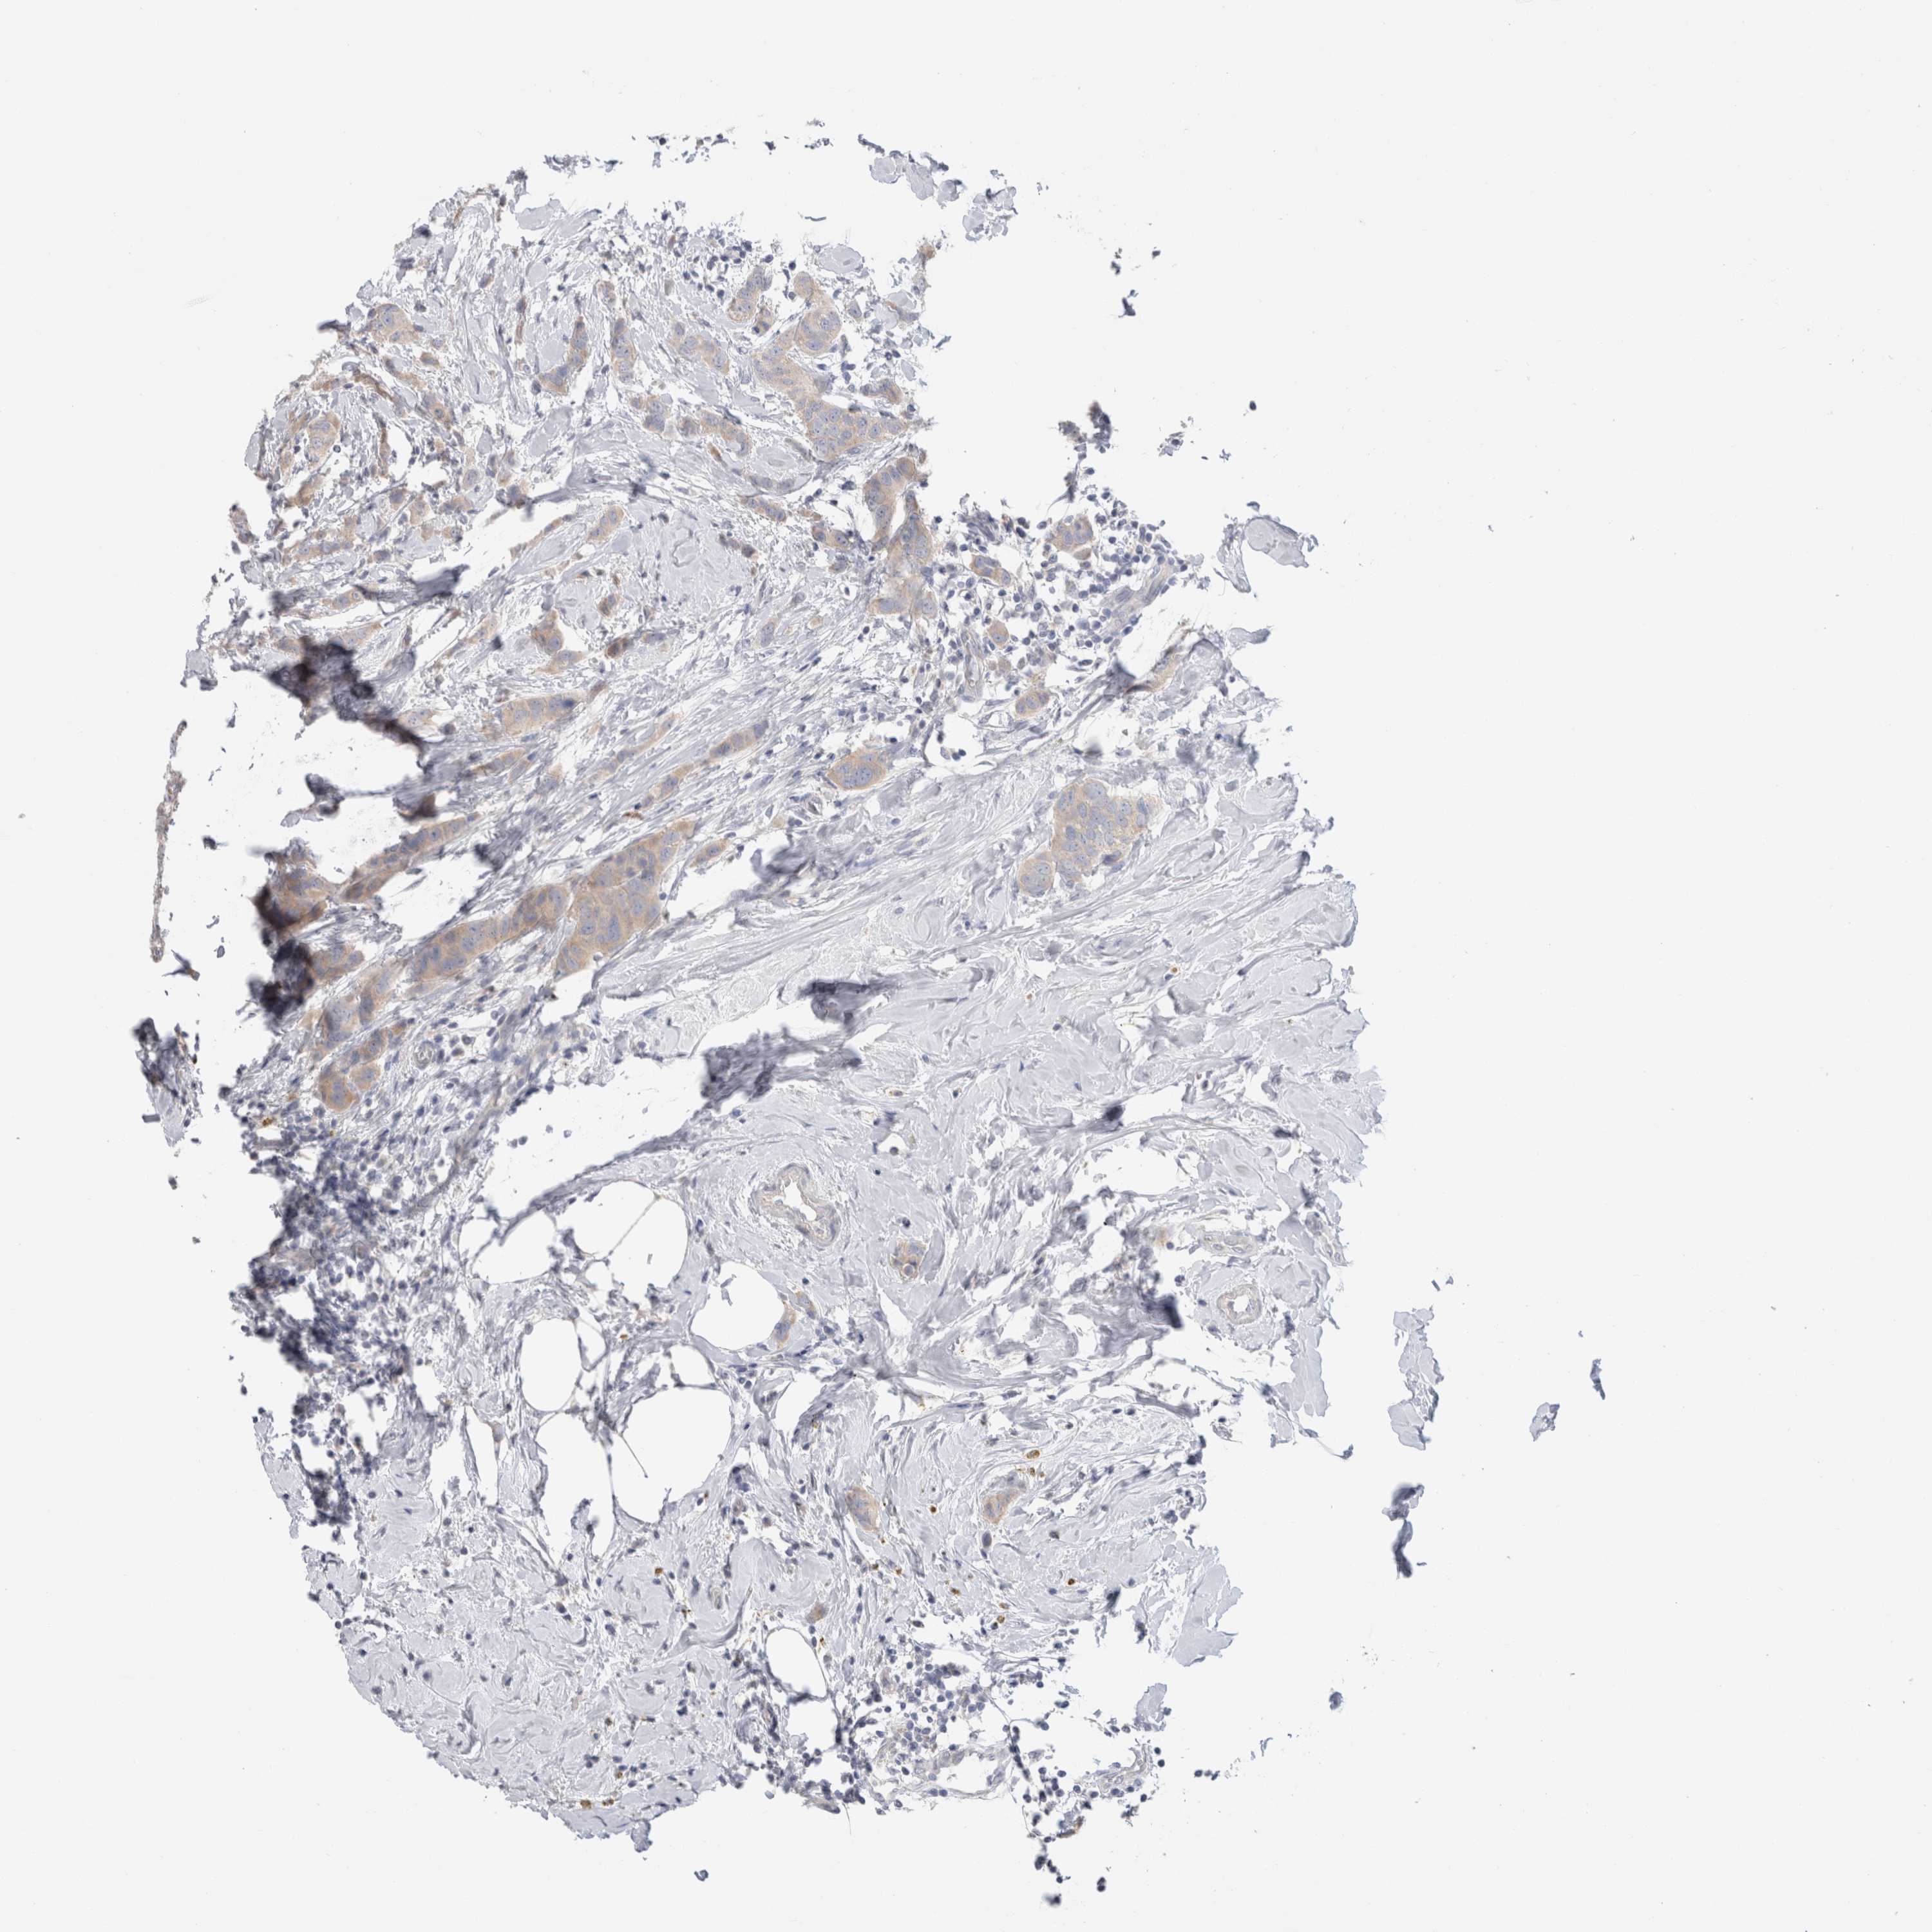

CANCER BREAST CANCER Show tissue menu

BRCA TCGA BRCA VALIDATION PROTEIN EXPRESSION